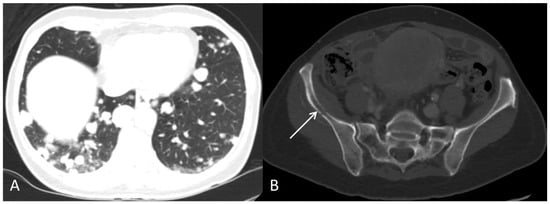

Figure 5. (A) Follow-up axial PET/CT fused and (B) axial CT after three series of chemotherapy shows progression with multiple metastases in both lungs.